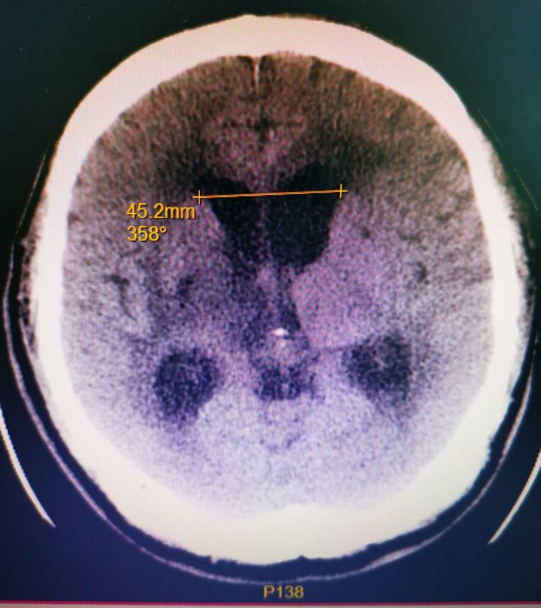

▲术前影像

7月初王先生在我院神经外科被诊治为梗阻性脑积水,经过头颅CT和核磁的完善评估,证实脑室内有粘连影响脑脊液循环出现脑积水,王先生逐渐精神萎靡意识障碍加重、并伴有恶心、呕吐,情况十分危急。经神经外科团队详细检查和病情讨论后,决定进行手术治疗。